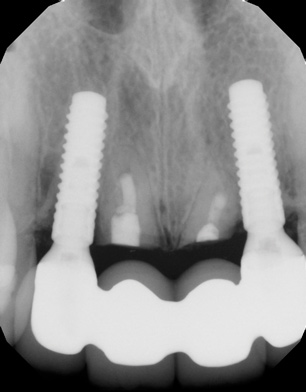

Fig 19. Radiograph 3 years postoperative of Nos. 7 through 10 implant restoration described in Fig 17 and Fig 18.

Figure 19

Fig 17. Facial (Fig 17) and occlusal (Fig 18) views, 3 years postoperative, of implants Nos. 7 and 10, fully guided with 3D placement of 3.3-mm x 12-mm implants with non-loading of both sites. Patient was high esthetic risk profile. Key Nos. 7 (SCTG) and 8 (immediate contour management) were not used. Facial bony concavity with loss of ridge width was noted on No. 7 along with show-through of titanium abutments (periodontist: Jeff Ganeles, DMD).

Figure 17

Finally, another example of an "unlucky" esthetic outcomeis illustrated in Figure 17 through Figure 19, which show the 3-year postoperative follow-up of the fully guided (coDiagnostix®, Dental Wings, dentalwings.com) 3D placement of No. 7 and No. 10 implants (Straumann Bone Level Narrow Connection Roxolid® SLActive, Straumann) in a 34-year-old high esthetic risk profile female patient with non-loading of both implant sites. For this patient, eight of the 10 keys were followed, with the exceptions being key Nos. 7 (SCTG) and 8 (immediate contour management). Esthetic complication was noted, especially on implant No. 7, with a facial bony concavity with loss of ridge width and show-through of the titanium custom abutments (ie, "graying" of soft tissues) due to colorimetric changes of the marginal tissues.